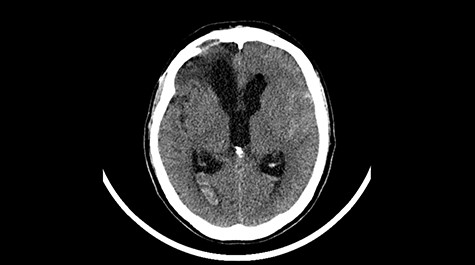

Head CT after polypectomy—seen sphenoid sinus and both maxillary sinuses filled with blood. (Department of Neurosurgery own material).

In described case, a head CT scan after polypectomy confirmed the subarachnoid hemorrhage (Fig. 1). In addition, the presence of air in the ventricular system was visible, and presence of defects of the upper left orbital wall and ethmoid on both sides (Fig. 3). In the CT scan sphenoid sinus, frontal and ethmoidal sinuses on both sides and right maxillary sinus airless, filled with blood and soft tissue. The changes also concerned the lateral part of the left maxillary sinus (Fig. 4).